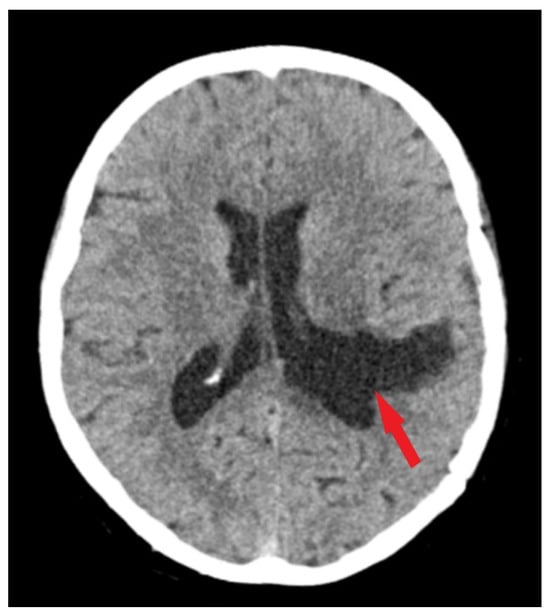

A brain MRI (i.e., multi-planar, multi-sequential brain MRI examination was performed on a General Electric 3T Signa Architect, Chicago, IL, USA) with contrast enhancement revealed an intraventricular tumor located in the body of the left lateral ventricle. The tumor presented as an ovoid, well-delineated mass with T1 hypointensity and T2 hyperintensity, measuring up to 60 mm in maximum diameter. It induced deformation of the left lateral ventricle. The tumor was associated with substantial digitiform edema, causing a shift in the midline structures and a potential risk of subfalcine herniation (Figure 1 and Figure 2).

Figure 1.

Preoperative MRI T1 and T1Gd sequence. Sagittal section of MRI T1 sequence (A) and axial section of MRI T1 Gd sequence (B), depicts an intraventricular mass into the left ventricle body (red arrows) with associated perilesional edema (blue arrow).